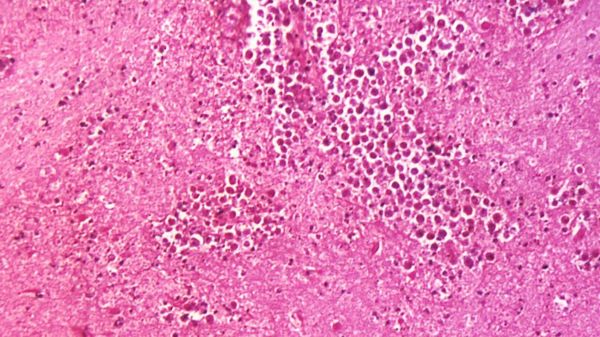

Попав в нос, паразит Неглерия Фоулера (Naegleria fowleri) по обонятельному нерву добирается до мозга и поражает мозговую ткань. При этом, как отмечают медики, пить зараженную бактерией воду не опасно. Главное – чтобы она не попала именно в нос.

Официальное название болезни, вызываемой этим одноклеточным микроорганизмом, – первичный амебный менингоэнцефалит.

Его симптомы могут включать в себя головную боль, резкое повышение температуры, тошноту, рвоту, потерю ориентации в пространстве, спазм затылочных мышц, судороги и/или галлюцинации.